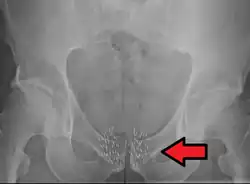

Znacznemu zaawansowaniu miejscowemu zwykle towarzyszą przerzuty odległe[185]. Rak gruczołu krokowego najczęściej daje przerzuty do węzłów chłonnych, kości i płuc[186]. Szerzenie się drogą naczyń chłonnych skutkuje zajęciem węzłów chłonnych[186]. Zajęcie poszczególnych grup węzłów chłonnych odbywa się zgodnie z drenażem limfatycznym narządu[187]. Przerzuty w węzłach chłonnych najpierw stwierdza się w grupach węzłów poniżej rozwidlenia tętnicy biodrowej wspólnej: w węzłach biodrowych wewnętrznych i biodrowych zewnętrznych, następnie dochodzi do zajęcia węzłów biodrowych wspólnych, okołoaortalnych i pachwinowych[186]. Rozsiew drogą krwionośną skutkuje powstaniem przerzutów odległych, które najczęściej pojawiają się w szkielecie osiowym, a rzadziej w płucach, wątrobie i innych narządach[147]. Przerzuty w kościach zwykle mają charakter osteoblastyczny (80%), ale możliwe są zmiany osteoblastyczno-osteolityczne (15%) i osteolityczne (5%)[187][185]. Przerzuty kostne często lokalizują się w kręgosłupie, szczególnie w odcinku lędźwiowym i piersiowym, nasadach kości udowych, miednicy, żebrach, mostku i czaszce[185][186][154][187]. Przerzuty do płuc, wątroby i innych narządów występują raczej w późnym przebiegu choroby i dotyczą one odpowiednio 25% i 20% chorych[186][187].

ETS

Rodzina czynników transkrypcyjnych ETS wpływa na wiele procesów komórkowych, w tym proliferację, różnicowanie, apoptozę i angiogenezę[199]. Translokacja obejmująca gen kodujący czynnik transkrypcyjny ETS jest jedną z najczęstszych mutacji w raku gruczołu krokowego u ludzi[200]. Ocenia się, że występuje w 20% przypadków PIN i 50% przypadków gruczolakoraka[188][201]. W wyniku translokacji genu czynnika transkrypcyjnego z rodziny ETS i połączenia z zależnym od receptora androgenowego promotorem TMPRSS2 powstaje gen fuzyjny, który ulega nadekspresji i dereguluje wiele szlaków istotnych w karcynogenezie. W 90% rearanżacja ETS obejmuje gen ERG, rzadziej dochodzi do translokacji genu ETV1, ETV5 czy ETV4. Gen ERG zwykle ulega połączeniu z genem TMPRSS2, choć zidentyfikowano również inne geny regulowane androgenami, które ulegają fuzji z genem ERG[200]. Rola rearanżacji ETS w raku gruczołu krokowego jest niejasna. Sama nadekspresja ETS jest niewystarczająca do powstania raka i do powstania nowotworu konieczna jest akumulacja kolejnych mutacji[199][188].

Receptor androgenowy (AR)